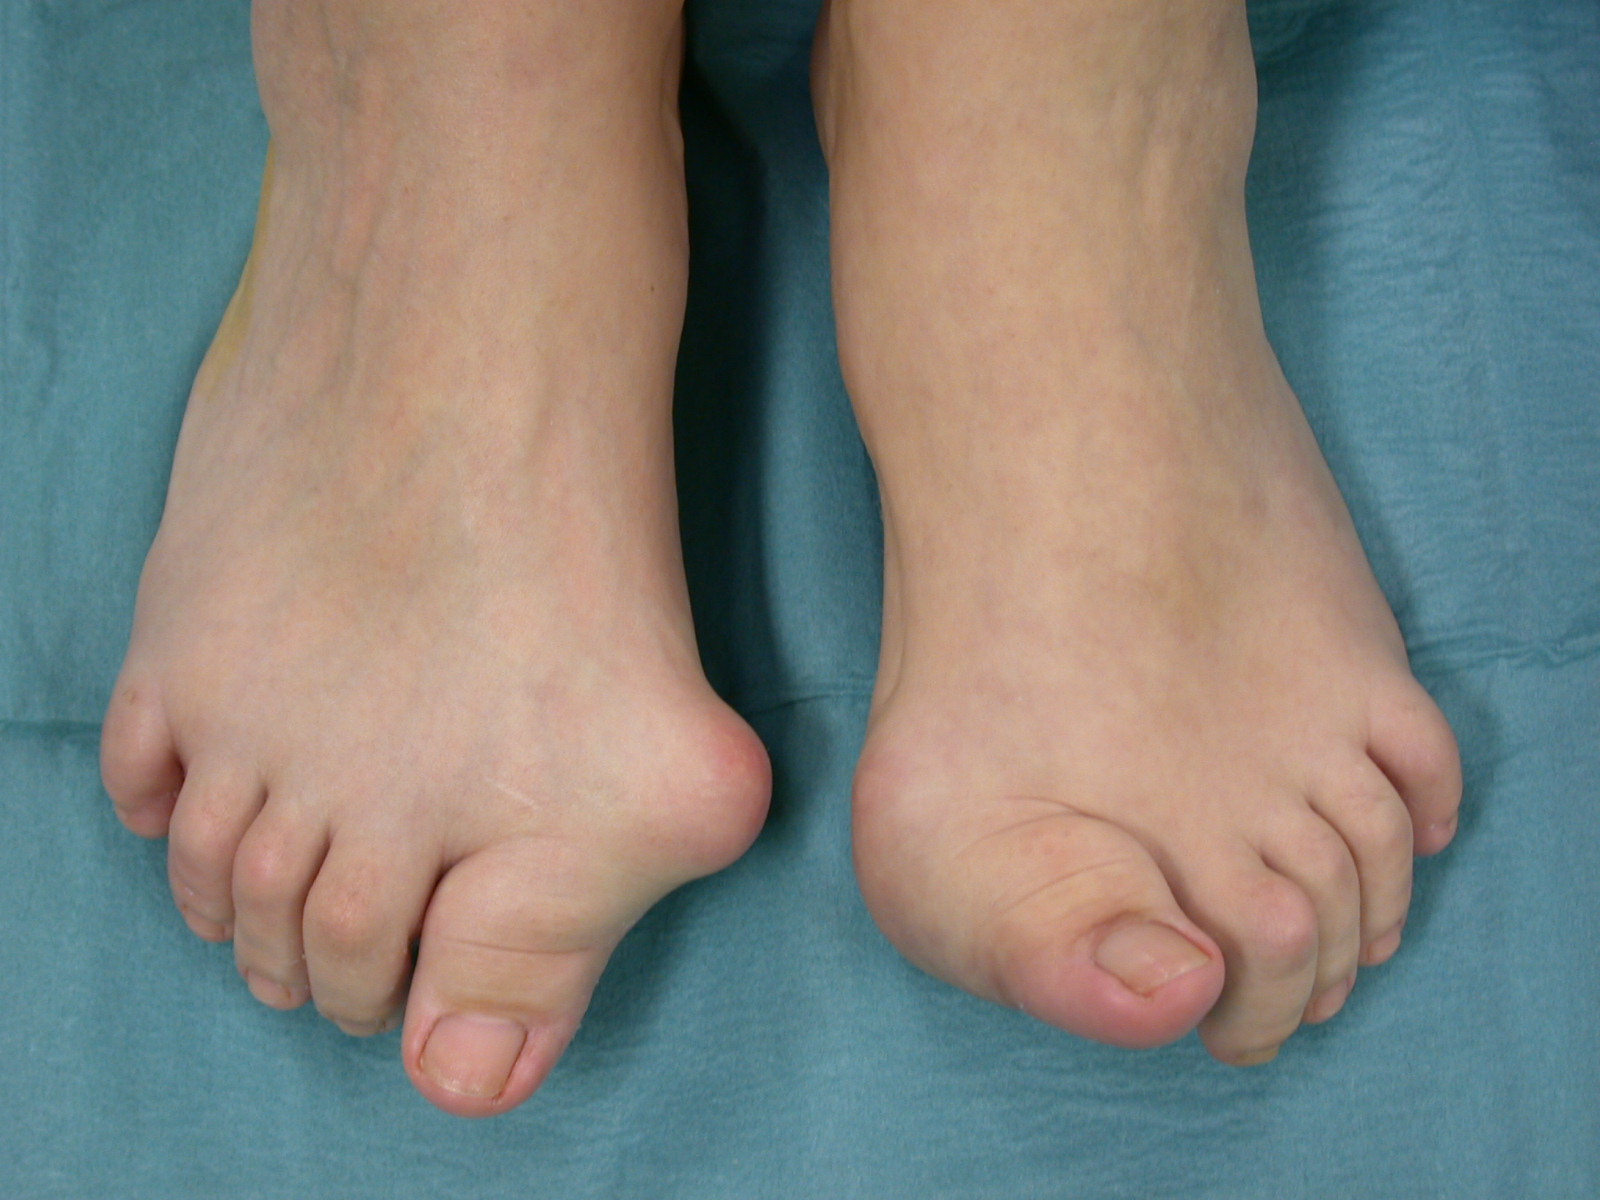

Tipicamente l’esordio è caratterizzato da dolori articolari accompagnati da tumefazione e rigidità che interessano le articolazioni di mani e piedi in maniera simmetrica ed aggiuntiva (cioè interessamento di altre articolazioni senza regressione nelle sedi già colpite). A livello del piede le articolazioni più frequentemente interessate sono le metatarso-falangee cioè le articolazioni alla base delle dita che vanno spesso incontro a lussazione patologica ; con minor frequenza sono interessate le articolazioni del retropiede e della caviglia (tra astragalo e scafoide , tra astragalo e calcagno, tibiotarsica). Se non adeguatamente trattata compaiono ipertrofia sinoviale ed erosioni dei capi articolari che comportano caratteristiche deformità ; in particolare all’avampiede si realizza spesso deformità in valgismo (cioè verso l’esterno) dell’alluce e delle dita laterali. Al retropiede il problema più comune è la comparsa di un progressivo piattismo che può arrivare a situazioni molto gravi per instabilità delle articolazioni interessati e per progressivo cedimento delle strutture tendinee , in particolare del tibiale posteriore.